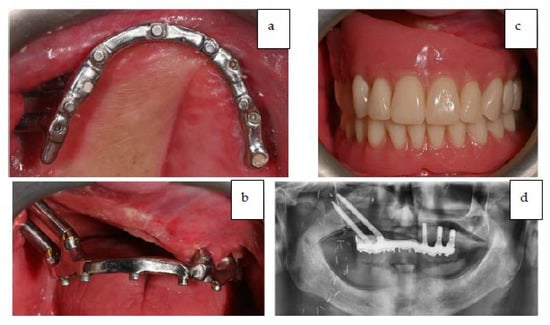

The occlusion and prosthesis were checked at a follow up on the 7th post-operative day. The patient underwent a cycle of radiotherapy without any complications or dehiscence of the flaps. The final fixed prosthesis was delivered 8 months after the surgical intervention. The definitive final removable prosthesis was retained by an implant-supported titanium bar that allowed the patient to have a strong and stable occlusion during function and provided easy access for oral hygiene. The patient reported a complete satisfaction from phonetic, functional, and aesthetic points of view. Figure 17a–d shows the final prosthesis (Note on Figure 17: The evolution of the oro-naso-sinusal defect repair through the soft tissue graft was uneventful without any complications. As can be seen in Figure 17, the tissue was œdematic for the first weeks and slowly shrank to healthy dimensions after healing).

Figure 17.

(a–c) Intra-oral occlusal and frontal view of the titanium bar retaining the definitive prosthesis and final prosthesis in occlusion. (d) Panoramic X-ray showing final prosthetic rehabilitation in place.